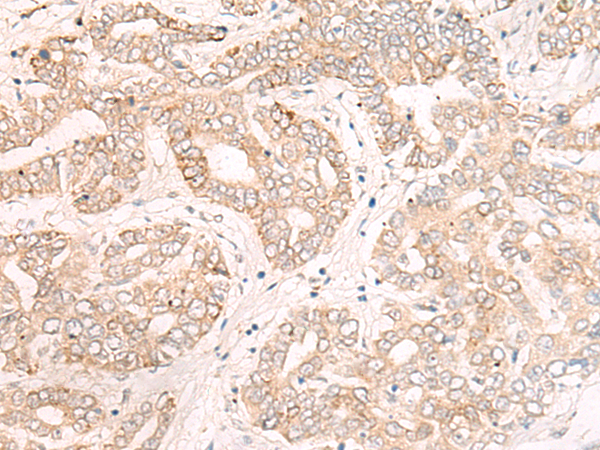

分类: 科研抗体货号: P06442别名: IL-34; C16orf77应用: WB,IHC反应种属: Human